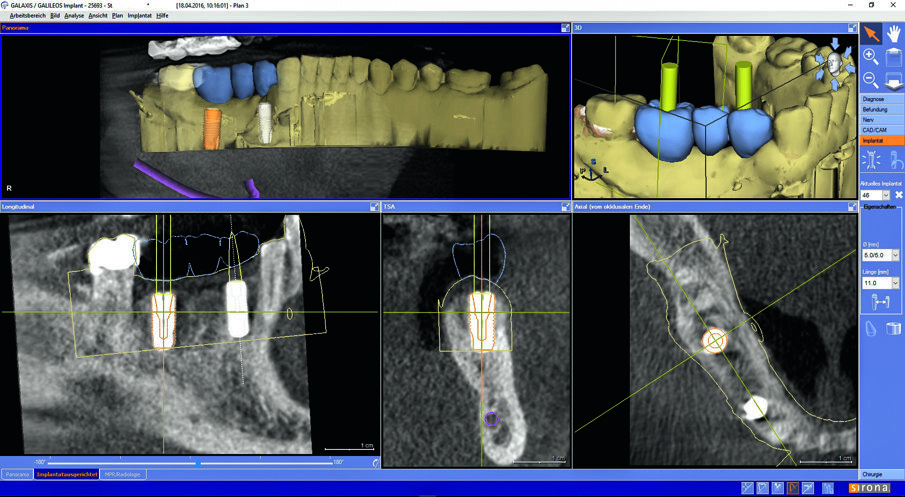

The patient opted for a treatment plan involving the insertion of two implants and then an implant-supported bridge. Digital imaging, combining DVT with CEREC optical impressions were used to plan the implant surgery in Galileos Implant software. The software creates an implant proposal as well as enables planning of the alignment of the prosthetic. The ability to plan and perform virtual surgery allowed the team to maximise safety and minimize risk. CEREC Guide 2 was chosen in the treatment plan and then milled in our practice to use during surgery.

Matching of Orthophos SL 3D data with the prosthetic proposal in Galileos Implant.

Prosthetic alignment of the implant in planning.

By means of a low-dose recording, the implant was checked three-dimensionally.